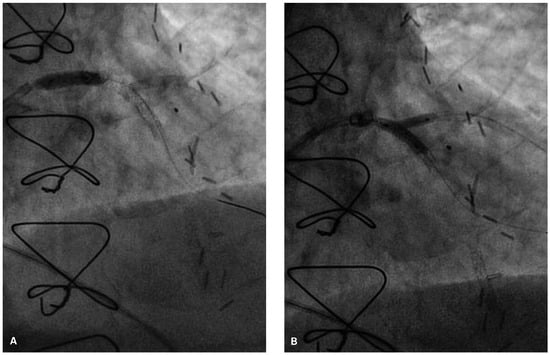

Coronary angiography of the left coronary system demonstrated severe left main stem (LMS) disease (Figure 1). The severe LAD in-stent restenosis was very eccentric and appeared to be restricting the origin of a sizeable diagonal branch, which also had severe disease. Distally, the LAD was occluded at the point where another stent had been inserted previously and just beyond a large septal perforator. The Cx had severe ostial disease and gave rise to a heavily diseased first obtuse marginal branch. The remainder of Cx and right coronary artery (RCA) systems were occluded proximally, with absent collaterals. The only patent graft was the LIMA, anastomosed very distally to the LAD (Figure 2). Following discussion, it was felt that neither Cx nor RCA were suitable targets for surgery and we therefore undertook intervention to the LMS and LAD / first diagonal bifurcation.

Figure 2. Straight PA view of the LIMA anastomosis to distal LAD.